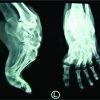

A 19-year-old female presented with history of pain in the left ankle since 10 months. Pain had gradually increased over the time so that, at the time of presentation, the patient had restricted daily activities. She also had swelling over left ankle region since last 3 months. On examination, swelling and tenderness of ankle were present. Subtalar and ankle joint movements were painful and restricted. Plain radiographs of the ankle revealed expansile osteolytic lesion of the talus which had expanded whole of the talus and the bony cortices were thinned out but were not broken (Fig. 1). CT scan of ankle showed thinning of all the cortices, but no evidence of cortical break or soft-tissue extension was found (Fig. 2).

Patient’s hemoglobin, white blood cell count, and erythrocyte sedimentation rate were normal. Fine-needle aspiration cytology from the lesion showed giant cell rich lesion of the bone. The patient was posted for surgery. By anterior approach, talectomy was done. Then, tibiocalcaneal fusion was done using external fixator without using bone graft (Fig. 3). Post-operative period was uneventful. Histopathological examination proved the lesion to be giant cell tumor. External fixator was removed at 3 months and the patient was advised full weight-bearing along with the use of ankle-foot orthosis. There is no evidence of recurrence at 9 years of follow-up.